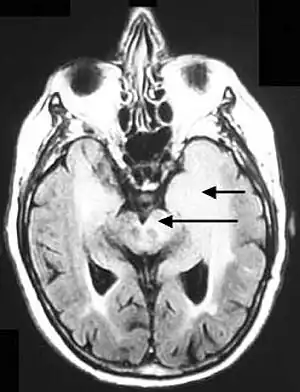

Fluid-attenuated inversion recovery (FLAIR) is an MRI sequence with an inversion recovery set to null fluids. For example, it can be used in brain imaging to suppress cerebrospinal fluid (CSF) effects on the image, so as to bring out the periventricular hyperintense lesions, such as multiple sclerosis (MS) plaques.[1] It was invented by Graeme Bydder. FLAIR can be used with both three-dimensional imaging (3D FLAIR) or two dimensional imaging (2D FLAIR).

Axial fluid-attenuated inversion recovery MRI image demonstrating tumor-related infiltration involving both temporal lobes (Short arrow), and the substantia nigra (Long arrow).